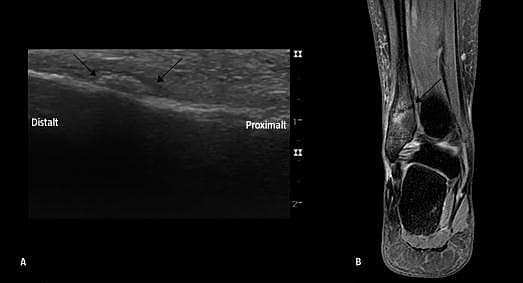

En 39-årig kvinde fik, da hun begyndte at løbetræne, ømhed i højre ankel. Under intervaltræning opstod der stærke smerter ved den laterale malleol med efterfølgende hævelse uden misfarvning - der var intet traume involveret. Grundet fortsatte gener blev der taget røntgen (Rtg) i tre plan ti dage efter symptomdebut, i.a. Elleve dage senere blev patienten set til idrætsmedicinsk vurdering. Man fandt her hævelse og direkte ømhed 4 cm proksimalt for spidsen af den laterale malleol. Ved området med maksimal ømhed blev der ved ultralyd (UL) fundet tegn på periostalødem, callusdannelse (A) og inflammation påvist med Doppler. Fundene var forenelige med stressfraktur i den laterale malleol, og patienten fik anlagt aircast -skinne. Der blev taget Rtg i tre plan samme dag, i.a. To uger senere blev der foretaget magnetisk resonans (MR)-skanning, og her sås fraktur i den distale fibula (B).

MR anses for at være guldstandard for tidlig diagnose af stressfrakturer, hvor Rtg først er anvendelig i senere faser [1]. UL er påvist at have bedre sensitivitet (83%) og specificitet (76%) ved diagnostik af stressfrakturer end MR [2]. Knogleskintigrafi anvendes også i denne diagnostik, men sammenlignet med UL er den væsentligt dyrere, involverer radioaktivitet og er mere tidskrævende.

Denne sygehistorie bekræfter effektiviteten af UL i tidlig diagnostik af stressfrakturer uden røntgenforandringer. UL kan med fordel implementeres i algoritmen for tidlig diagnostik af stressfrakturer som et sufficient og billigere alternativ til MR-skanning og knogleskintigrafi.